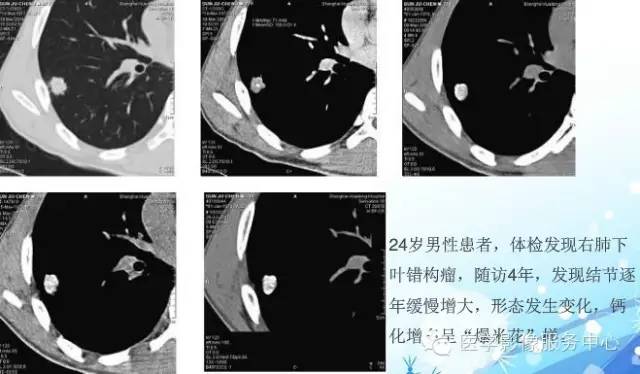

错构瘤的发病年龄多数在40岁以上,男性多于女性。 绝大多数错构瘤(约80%以上)生长在肺的周边部,紧贴于肺的脏层胸膜之下,有时突出于肺表面。其特征钙化为爆米花样钙化,内有脂肪软骨成分等等。最常见的部位是胸膜下肺实质内,其次为主支气管或肺叶、肺段支气管内。

瘤内出现“爆米花样钙化”是诊断的主要指标之一。早期的点状、斑片状及结节状钙化 随时间增加钙化数量及范围会增加,最终可能演变 为爆米花样钙化;